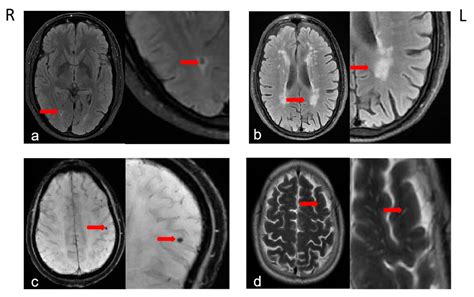

Diagnosis is usually confirmed via an MRI of the brain, which provides a detailed look at the white matter. Radiologists look for specific patterns, such as leukoaraiosis or hyperintensities, which appear as "bright spots" on the scans. These spots indicate areas where the brain tissue has been affected by chronic ischemia.

White Matter Hyperintensities (WMH) Indicates long-term vascular stress and potential cognitive slowing.

Lacunar Infarcts Small, fluid-filled cavities resulting from past tiny strokes.

Microbleeds Tiny hemorrhages indicating fragile vessel walls.

Brain Atrophy Loss of overall brain volume, often associated with advanced disease.